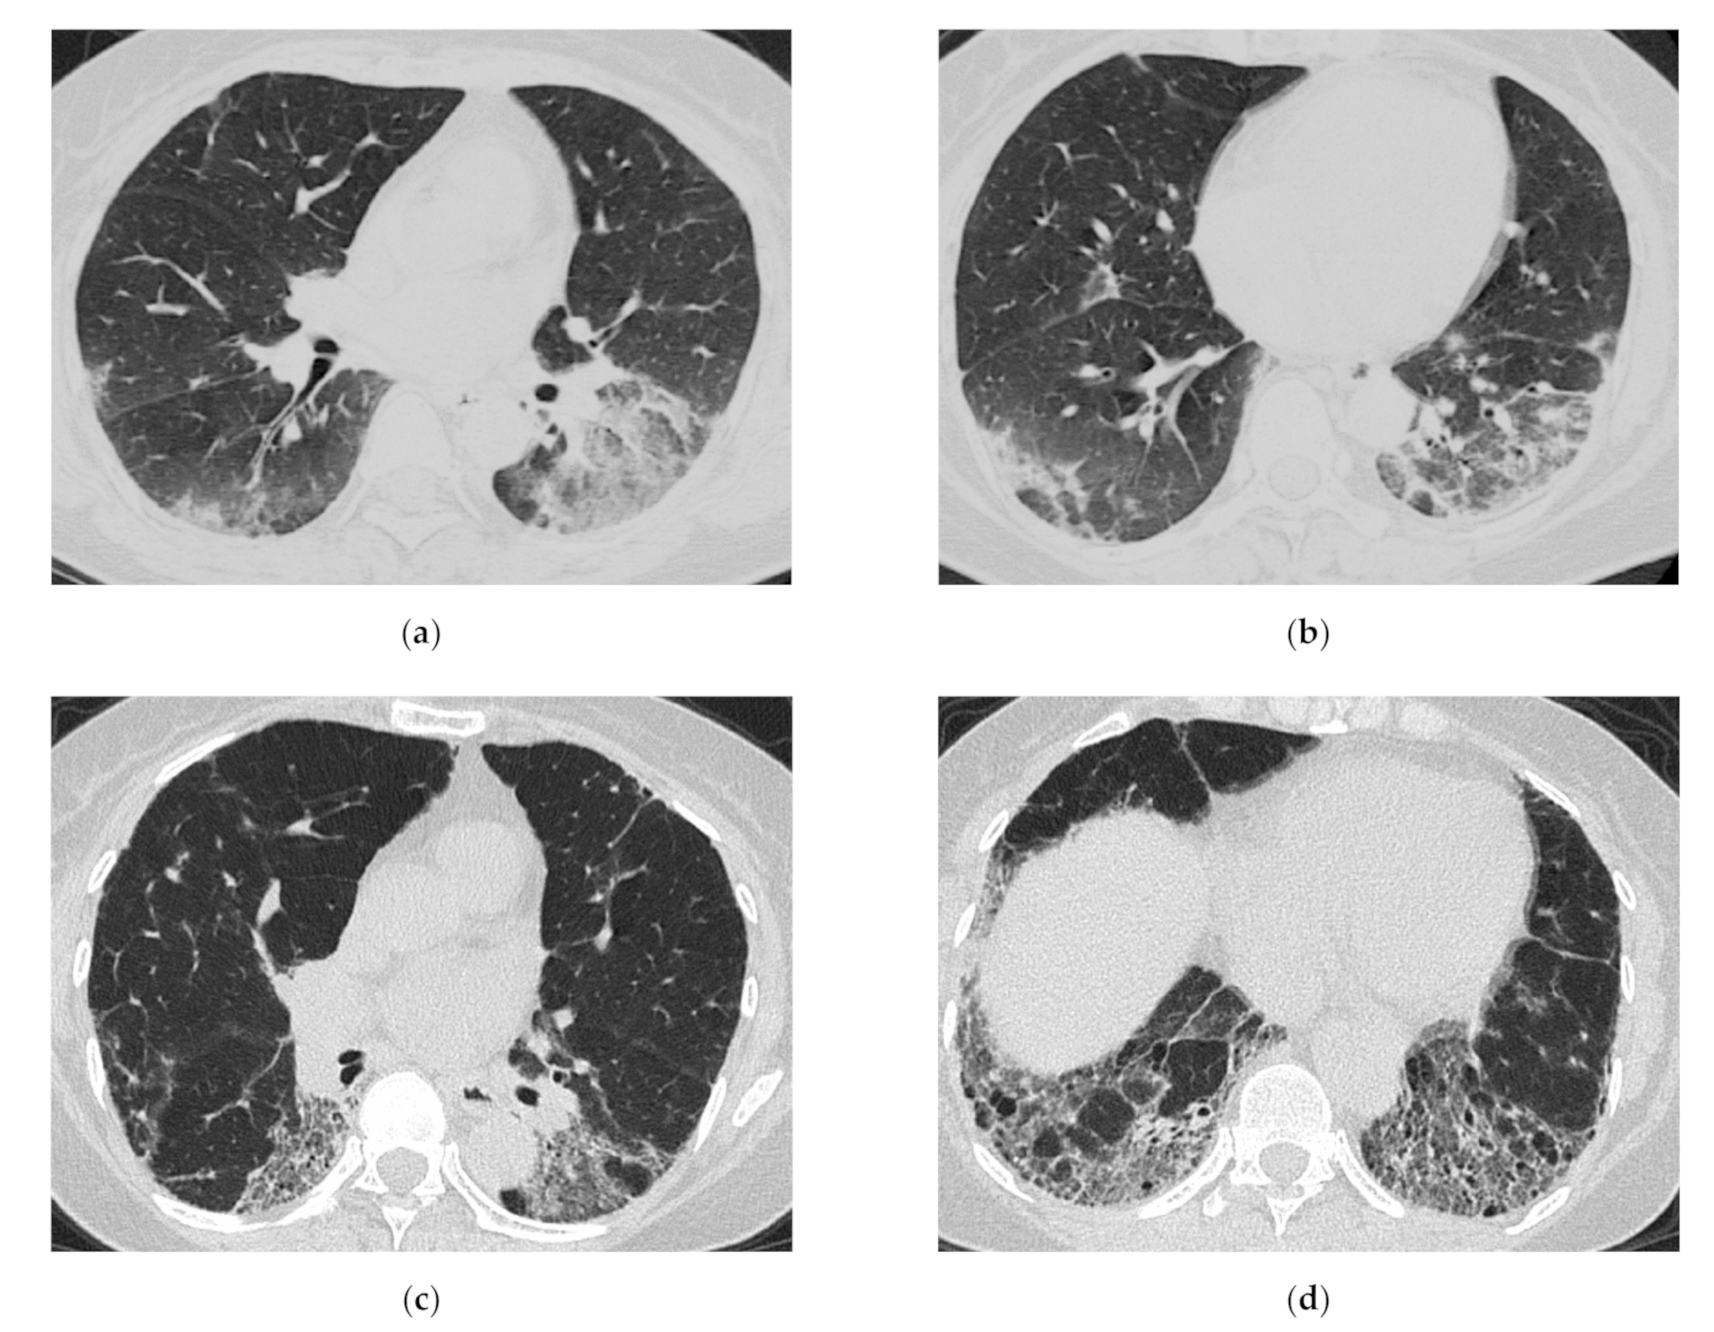

HRCT Findings of Patients with Anti-ARS Ab

| Anti-ARS Antibody Positive | Anti-MDA5 Antibody Positive |

|---|---|

| Chronic to subacute onset >> Acute/rapidly progressive | Acute or subacute onset, often rapidly progressive |

| Distribution along the bronchovascular bundles in the bilateral lower lung fields > diffuse | Diffuse, predominantly in the lower lung fields, or both |

| Reduced volume of the lower lobes | Peribronchovascular lesion of the periphery of lower lobes, with parallel spread to the pleura |

| Reticular shadows or consolidation > GGO | Patchy distribution |

| Good response to treatment but relapses | GGO and consolidation |